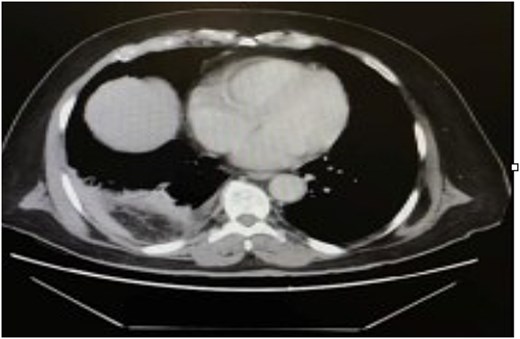

The patient was initially resuscitated with intravenous fluids. An urgent abdominal computed tomography (CT) scan was performed, revealing a herniated and obstructed segment of large bowel loops with mesenteric fat at the hepatic flexure, likely through the posterior right hemidiaphragm (Fig. 1). The scan showed a proximally dilated cecum and ascending colon, with a transitional zone observed at the neck of the hernia, leading to a distally collapsed colon. Additionally, there was an area suspicious for pneumatosis intestinalis within the obstructed bowel segment, along with adjacent fat stranding and free fluid—findings that raised concerns for strangulation or early ischemia. The scan also indicated a right-sided pleural effusion and adjacent atelectasis (Fig. 2).

CT scan of the abdomen revealed a herniated obstructed segment of large bowel loops and mesenteric fat at the hepatic flexure, likely through the posterior right hemidiaphragm.

CT scan of the thorax revealed a right-sided pleural effusion and adjacent atelectasis.